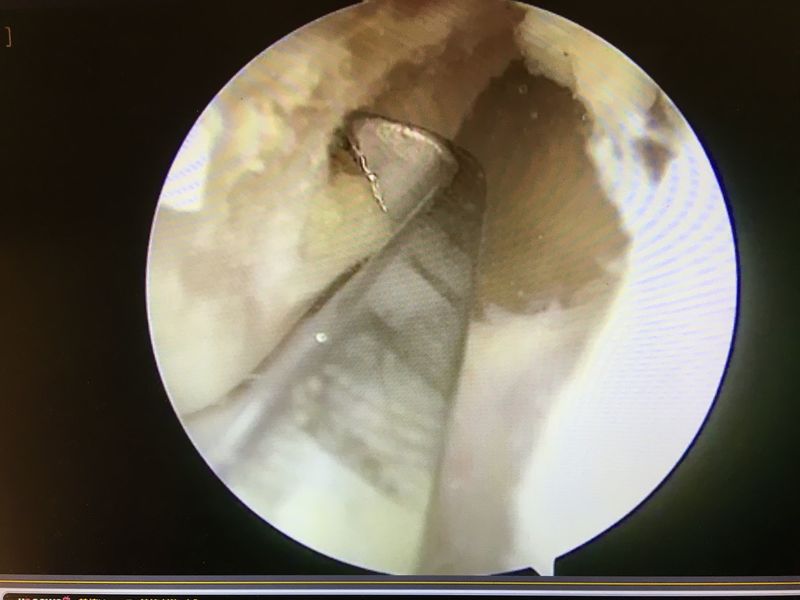

ACL再建

![]() | ![]() | ![]() |

| 大腿骨孔作成 | グラフト挿入 | 再建靭帯 |